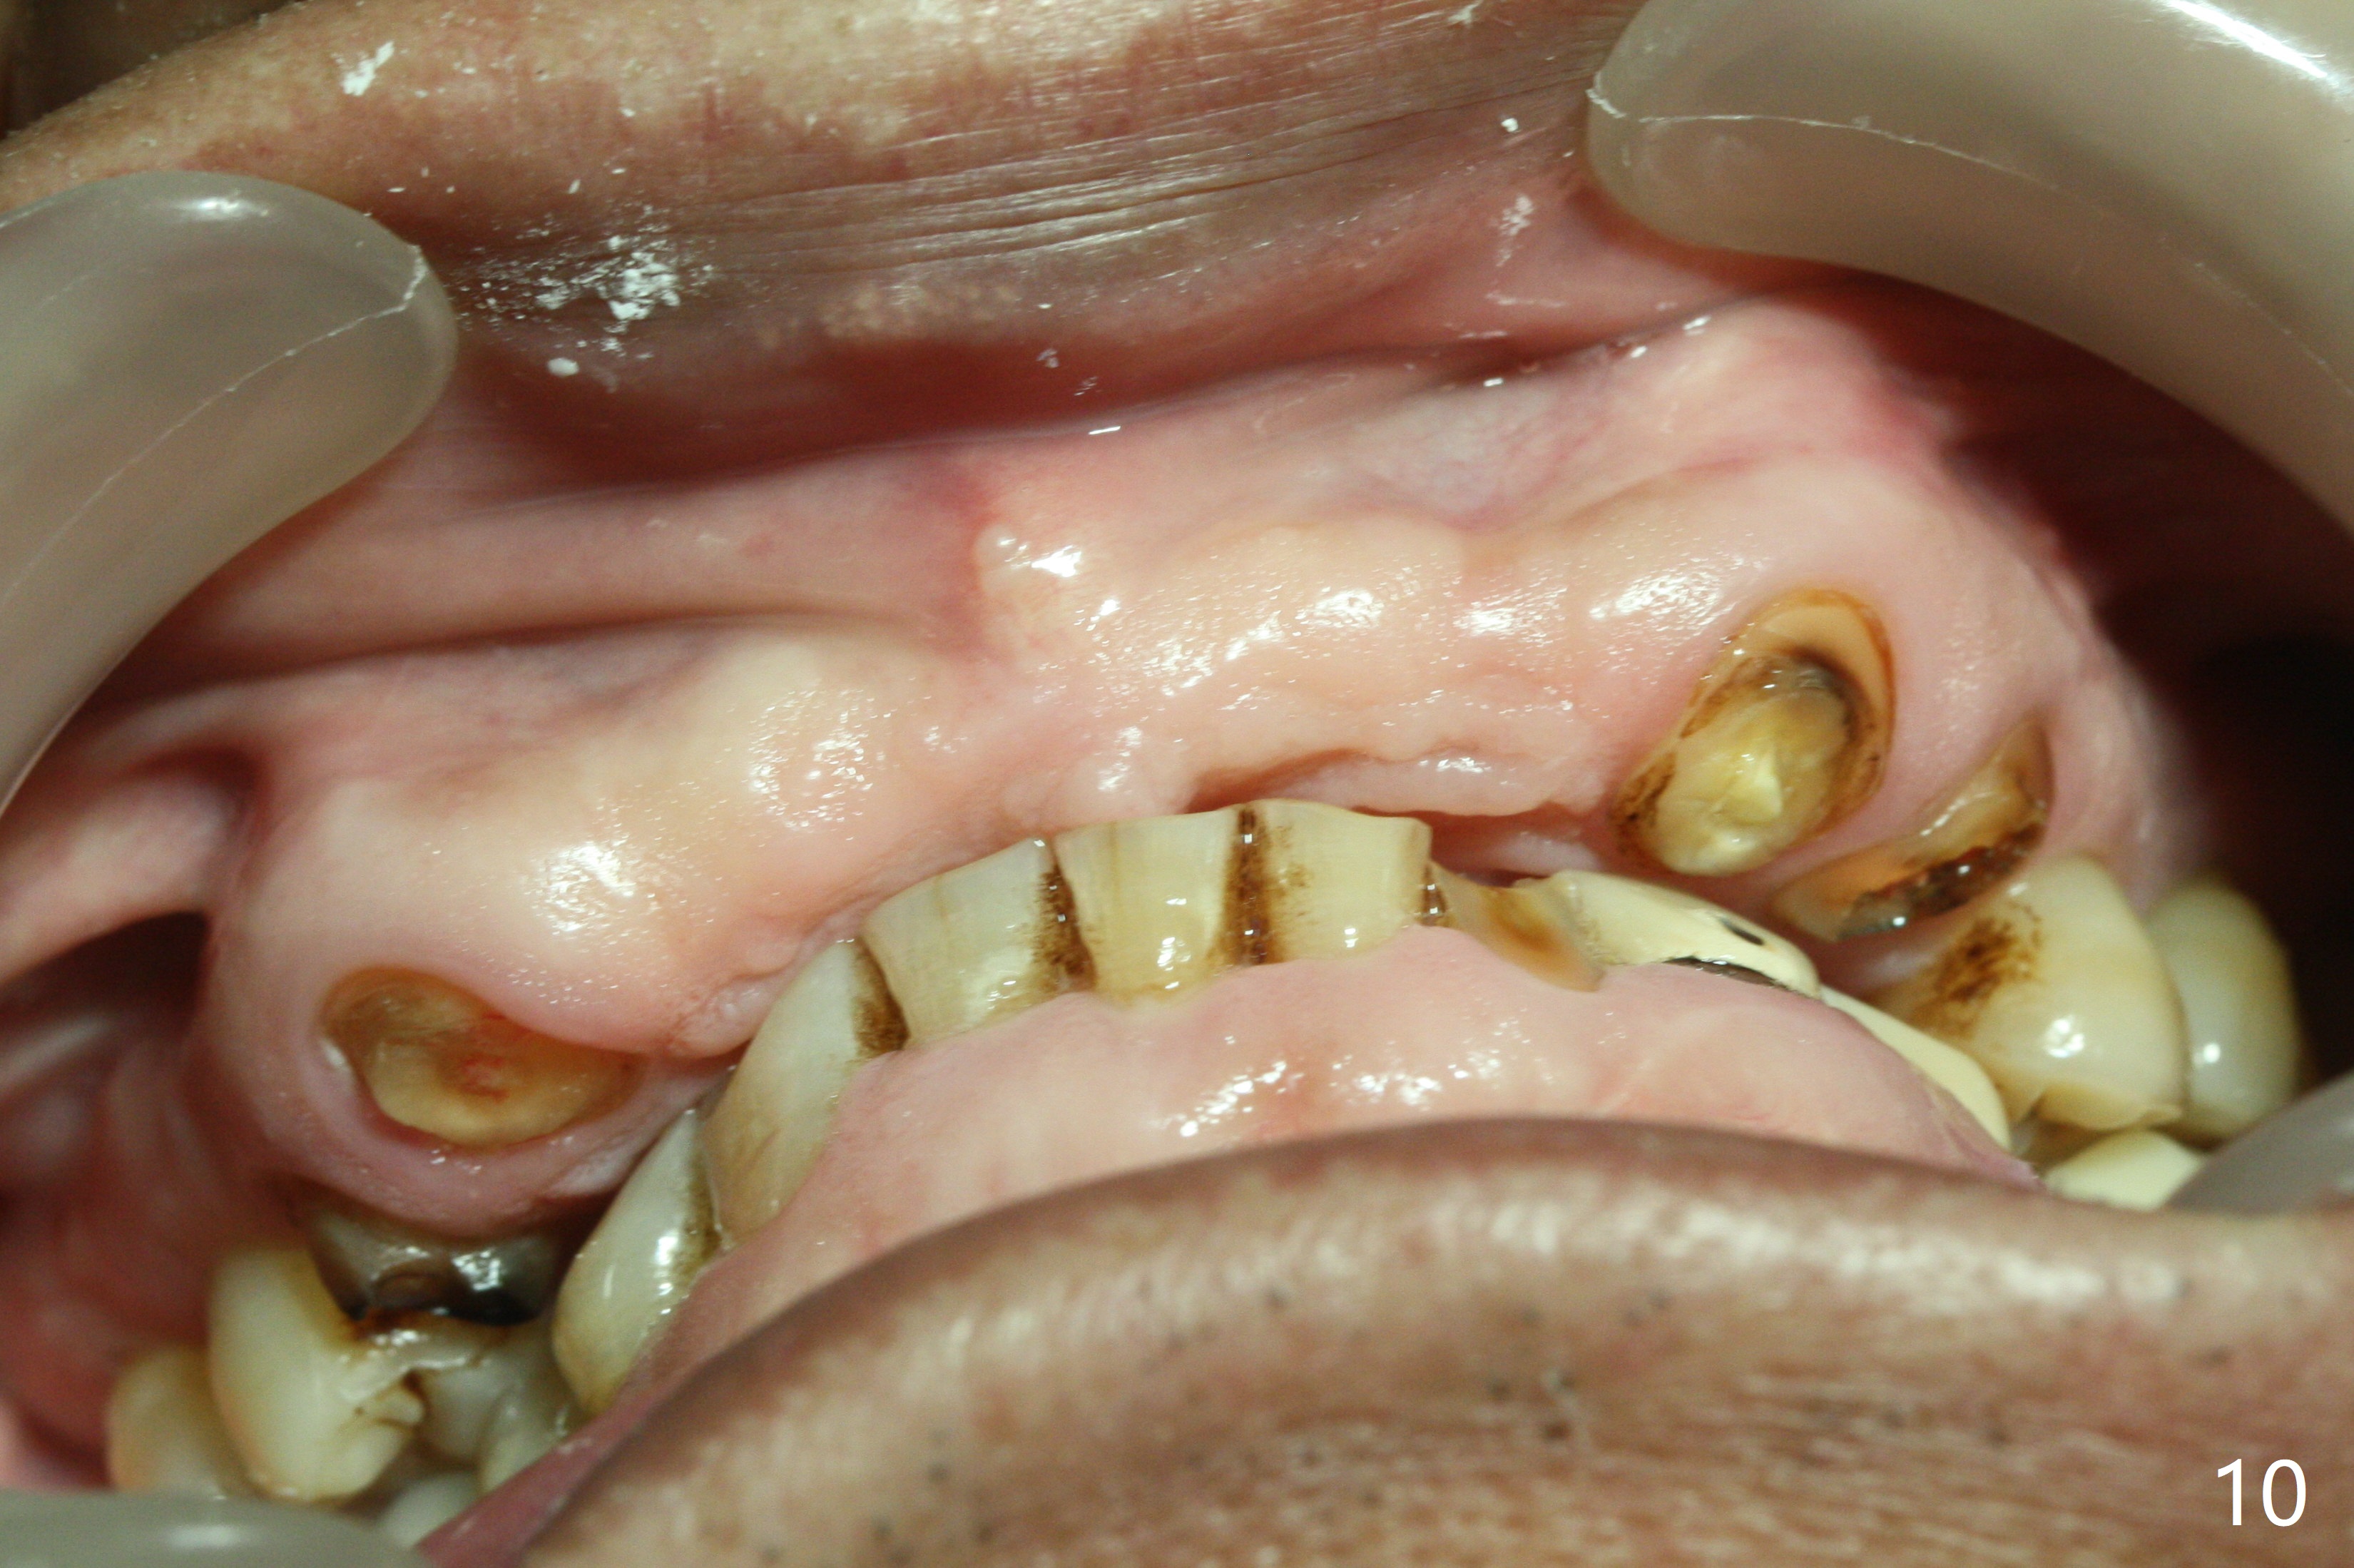

It is smooth and quick to finish osteotomy with guide at #6,7,10-12, but when 3 mm 1-piece implants are placed free hand at #7 and 10 (Fig.1,2), the gingival parts of the abutments contact the incisal edges of the lower incisors (anterior deep bite) in spite of effort to change the trajectory by repeated back and forth placement after use of Lindamann bur buccally. Following an immediate provisional (Fig.3,4), the occlusal surface of the posterior teeth are raised to eliminate anterior restoration interference. Immediate postop CBCT shows that the implants at #7 and 10 could be placed more buccally (Fig.6,7, as compared to the normal position at #6,11,12 (Fig.5,8,9)). Fig.10 was taken 2 days preop, while Fig.11-13 postop. Can we change 1-piece implants (3mm) at #7 and 10 to 2-piece one (3.5) and use angled or cementation abutments for easy restoration (Fig.14-16)?